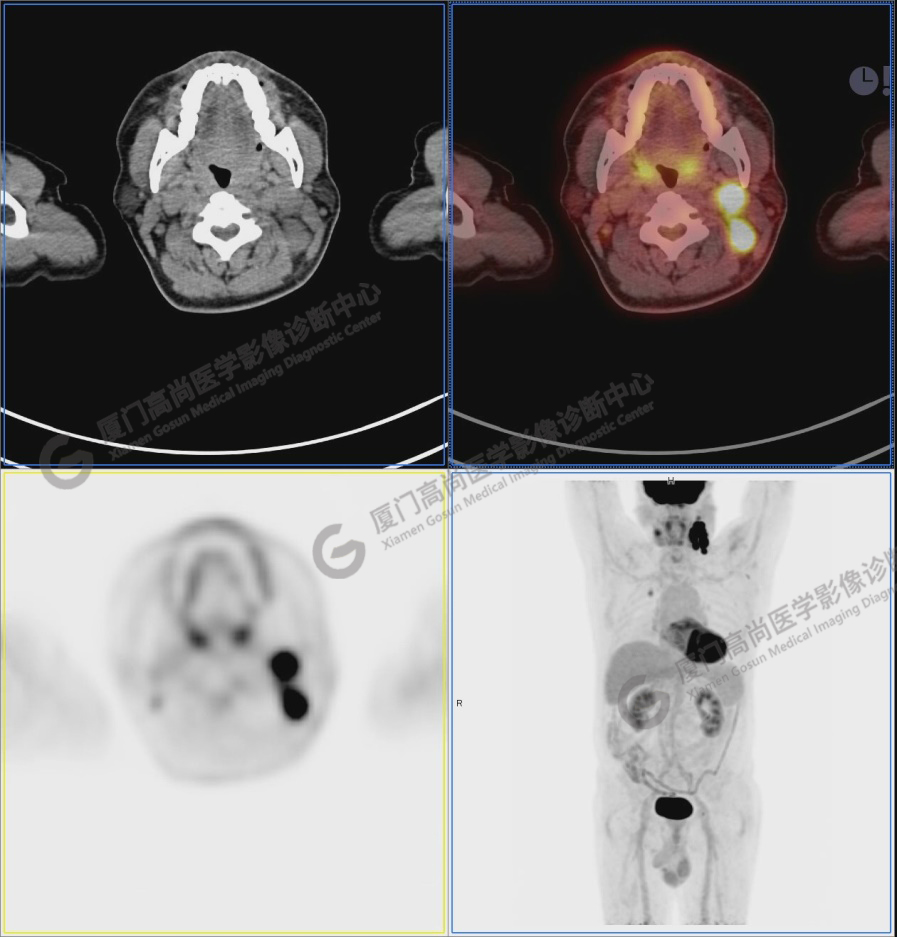

圖6-9:鼻咽左側(cè)壁增厚,代謝異常增高,考慮為鼻咽癌

圖2:雙側(cè)頸部多發(fā)增大淋巴結(jié),代謝不同程度增高,考慮為轉(zhuǎn)移。